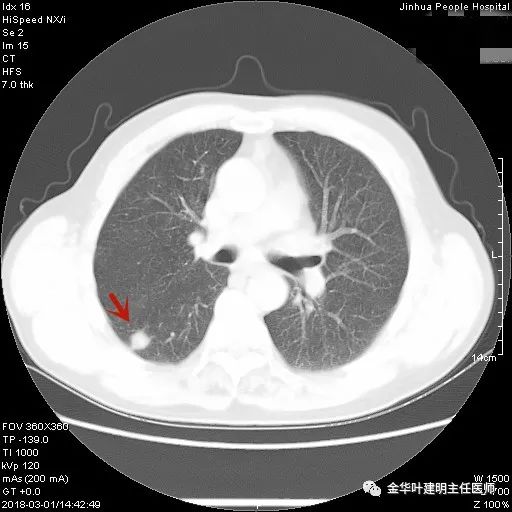

1、以下这种结节是体检发现中最常见的,它们基本上是良性的,可以年度复查:它们都是又上又实的微小结节,直径在5毫米左右或以下。实际上有许多非常焦虑的肺结节病友,他们很多人只是检查发现这种结节。我的建议是:年度复查!若实在不放心,也可半年时复查一次,以确定它不会生长。